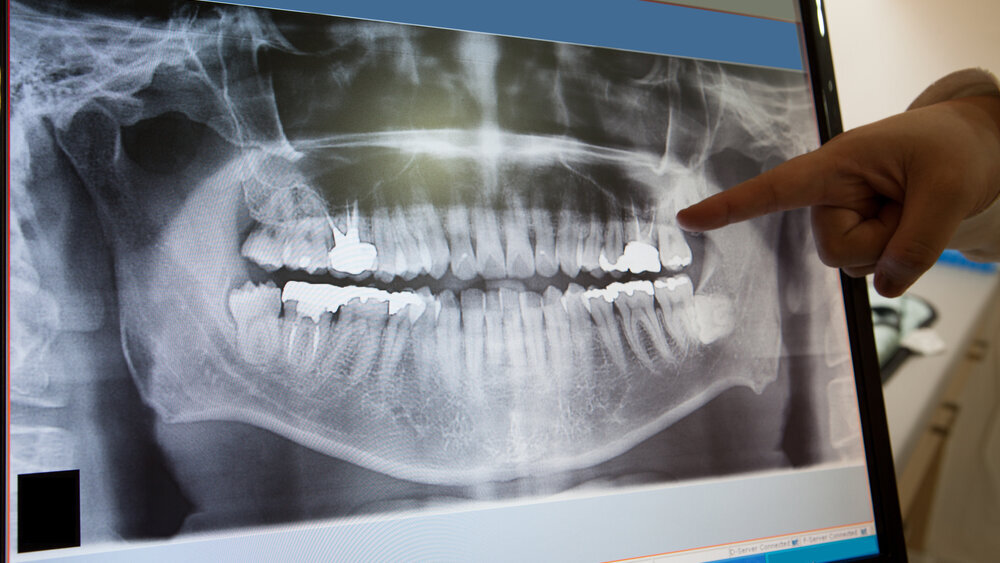

Πριν από 9 μήνες, πραγματοποιήθηκε πλήρης ψηφιακή μετατροπή του ιατρείου, που σημαίνει προσθήκη συστήματος ψηφιακής ακτινογραφίας. Είμαι ενθουσιασμένη με αυτή την επιλογή.

Επιτρέψτε μου να μοιραστώ ορισμένες από τις εμπειρίες μου και ελπίζω να σας διαφωτίσω σχετικά με τα οφέλη της ψηφιακής ακτινογραφίας.

Μόλις έμαθα να χρησιμοποιώ τη λειτουργία μεγέθυνσης των ακτινογραφιών, κατάλαβα πόσο σημαντικό ήταν αυτό το βήμα προόδου για το ιατρείο μου.